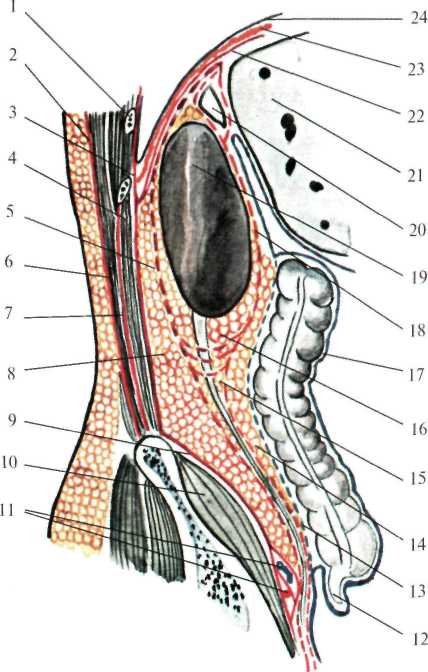

сзади – задней стенкой живота, т.е. позвоночником и мышцами поясничной области, выстланными внутрибрюшной фасцией (fascia endoabdominalis) (рис.2.3);

| Рис. 2.3. Слои поясничной области на сагиттальном срезе (схема). 1 – costa XI; 2 – lamina superficialis fascia thoracolumbalis; 3 – fascia endoabdominalis; 4 – m. quadratus lumborum; 5 – fascia retrorenalis; 6 – m. erector spinae; 7 – lamina profunda fascia thoracolumbalis; 8 – spatium retroperitoneale; 9 – fascia iliaca; 10 – m. iliacus; 11 – a., v. iliaca communis; 12 – processus vermiformis; 13 – fascia Toldi; 14 – paracolon; 15 – paraureter; 16 – paranephron; 17 – peritoneum; 18 – fascia prerenalis; 19 – ren; 20 – glandula suprarenalis; 21 – hepar; 22 – fascia diaphragmatica; 23 – diaphragma; 24 – pleura diaphragmatica. |

В забрюшинном пространстве залегают три слоя забрюшинной клетчатки: жировой слой забрюшинного пространства (textus cellulosus retroperitonealis), жировая капсула почки (capsula adipose renis,s. paranephron) и околоободочная клетчатка (paracolon).

Жировой слой забрюшинного пространства внутрибрюшной и позадипочечной фасциями. У средней подмышечной линии (место перехода париетальной брюшины с передней стенки живота на заднюю) этот жировой слой переходит в предбрюшинную жировую клетчатку.

Околопочечная жировая клетчатка заключена между листками почечной фасции (fascia renalis). Эта фасция вверху начинается на уровне X-XI ребер, с боков – от места перегиба париетальной брюшины, затем, расщепившись на два листка (fascia retrorenalis et fascia praerenalis), охватывает околопочечную жировую клетчатку (рис.2.4.).

Околоободочная клетчатка залегает впереди от переднего листка почечной фасции. Она ограничена: сзади – предпочечной фасцией, спереди – задней поверхностью ободочной кишки и листком париетальной брюшины. В верхних отделах околоободочная клетчатка доходит до корня брыжейки поперечной ободочной кишки, внизу заканчивается у слепой кишки справа и у места перехода нисходящей обододочной в сигмовидную ободочную кишку – слева. Кроме того, по задней поверхности восходящей и нисходящей ободочной кишки залегает позадиободочная фасция Толди (fascia Toldi), представляющая собой перерожденный слой соединительной ткани, в эмбриональном периоде служившей брыжейкой кишечника.

Таким образом, слои поясничной области, если рассматривать их снаружи внутрь, располагаются в следующем порядке.

Медиальный отдел: кожа; подкожная клетчатка; поверхностная фасция; глубокий слой клетчатки; поверхностный листок пояснично-грудной фасции; мышца, выпрямляющая позвоночник; глубокий листок пояснично-грудной фасции; квадратная мышца спины и большая поясничная мышца; поясничная и квадратная фасции (внутрибрюшная фасция); жировой слой забрюшинного пространства; задний листок почечной фасции; околопочечная клетчатка; почка; передний листок почечной фасции; околоободочная клетчатка; позадиободочная фасция (fascia Toldi); париетальная брюшина.

Латеральный отдел: кожа; подкожная клетчатка; поверхностная фасция; глубокий слой клетчатки; собственная фасция спины; широчайшая мышца спины; наружная косая мышца; задняя нижняя зубчатая мышца; внутренняя косая мышца; апоневроз поперечной мышцы живота; поперечная фасция; жировой слой забрюшинного пространства; задний листок почечной фасции; околопочечная клетчатка; почка; передний листок почечной фасции; околоободочная клетчатка; позадиободочная фасция (fascia Toldi); париетальная брюшина.